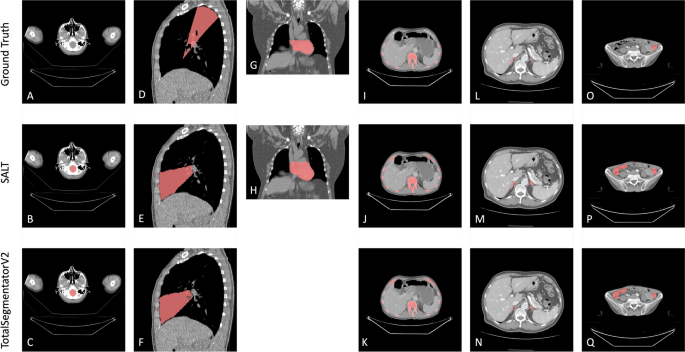

Comparison between the ground truth (first row), SALT (second row) and Version 2 of the TotalSegmentator (third row). The comparisons across various classes and datasets are systematically organized as follows: Figures (A), (B), and (C) focus on the comparison of the brain class from the CT-ORG dataset. Figures (D), (E), and (F) examine the middle lobe of the LUNA16 dataset. In Figures (G) and (H), the analysis shifts to the pericardium from the LCTSC dataset. The bone class from the CT-ORG dataset is compared in Figures (I), (J), and (K). Figures (L), (M), and (N) represent the adrenal glands from the FLARE22 datasets. Finally, Figures (O), (P), and (Q) compare the colon class from the WORD dataset.

The LUNA16 dataset demonstrated generally accurate lung segmentations, although the right middle lobe presented particular challenges. Both SALT and TotalSegmentator exhibited occasional misclassification of this region, resulting in a Dice score of 0.848 (see Supplementary Table S4). This highlights the challenges associated with segmenting lung regions with indistinct boundaries (Figs. 7E-F). The application of different annotation guidelines resulted in Dice scores of 0.894 for LCTSC and 0.952 for SAROS for the pericardium. There was a discrepancy between the annotations provided by LCTSC and those produced by SALT. LCTSC had annotated the heart around the pericardial sac, whereas SALT had segmented the entire area within the sac. This resulted in a mismatch (Fig. 7H). Furthermore, discrepancies were observed in the bone class; SALT achieved Dice scores of 0.911 in SAROS and 0.872 in CT-ORG. It should be noted that the SALT segmentation included cortical bone, which was not present in the CT-ORG or TotalSegmentator segmentations. Furthermore, SAROS annotated rib cartilage as bone, which differs from the approach taken by CT-ORG (Figs. 7I-K). The adrenal glands exhibited the lowest Dice scores (0.65–0.706), which can be attributed to SALT’s proclivity to incorporate surrounding tissue. Notwithstanding the discrepancies above, the high NSD scores (0.887–0.957) indicated accurate boundary alignment (Figs. 7L-N). Colon segmentation also presented difficulties, with occasional misidentification of air-filled small bowel sections as colon, particularly in cases of right hemicolectomy. This misclassification was observed in both SALT and TotalSegmentator, with Dice scores of 0.808 for SALT and 0.773 for TotalSegmentator (Figs. 7O-Q). These examples demonstrate the impact of anatomical variability and inconsistent annotation practices across datasets.

In general, SALT consistently achieved relevant results for key organs: kidneys (Dice 0.92, except CT-ORG), liver (Dice > 0.95), spleen (Dice > 0.92), stomach (Dice > 0.9), and lungs (Dice > 0.91, except right middle lobe). The adrenal glands were the most challenging, with Dice values of 0.65–0.70, but performed well in terms of NSD (0.88–0.95). SALT’s segmentation included more contours, which reduced the Dice scores for smaller classes such as the adrenal glands. In the SAROS dataset, SALT achieved results comparable to an nnUNet-based network for BCA, with a notable improvement in the mediastinum class (0.95 vs. 0.84) and only minor performance differences (up to 0.05) in most classes, except for the brain (nnUNet 0.97 vs. SALT 0.75). Comparisons with TotalSegmentator showed similar performance, with Dice differences within 0.05 for most classes, except for adrenals and vena cava in FLARE22 and kidneys and bladder in CT-ORG. Larger errors occurred in complex gastrointestinal classes such as the intestine and duodenum, which are challenging due to their anatomical variability and unclear boundaries. Differences in Dice scores between datasets also reflect different annotation guidelines and the inherent variability of human anatomy, as shown in Fig. 7 and Table S8. TotalSegmentator results highlight these discrepancies, such as Dice scores for adrenal glands (0.835 in FLARE22 and 0.624 in WORD), illustrating dataset-specific challenges.